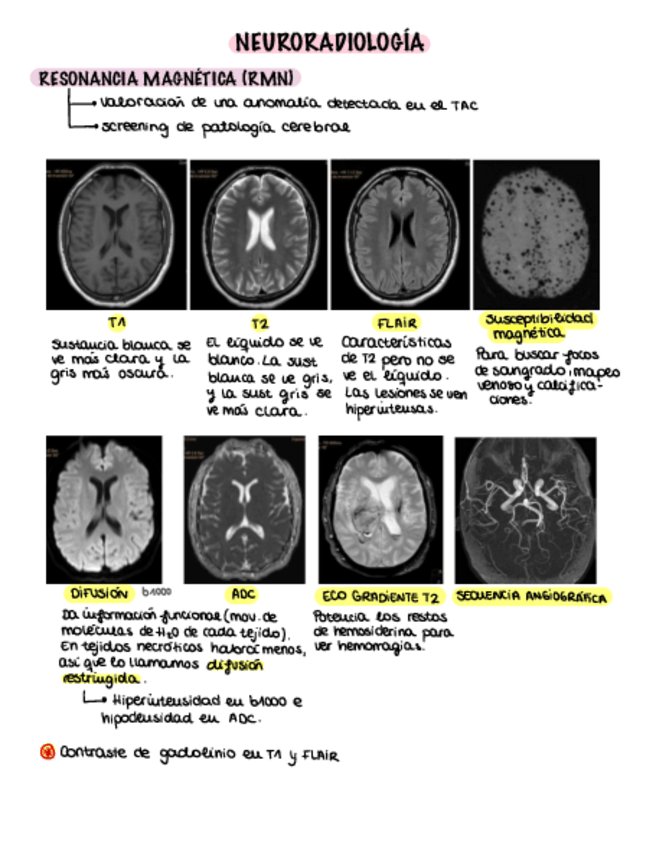

He publicado nuevos apuntes de 3º ESTUDIO POR LA IMAGEN: Apuntes-neuro.pdf

10 páginas